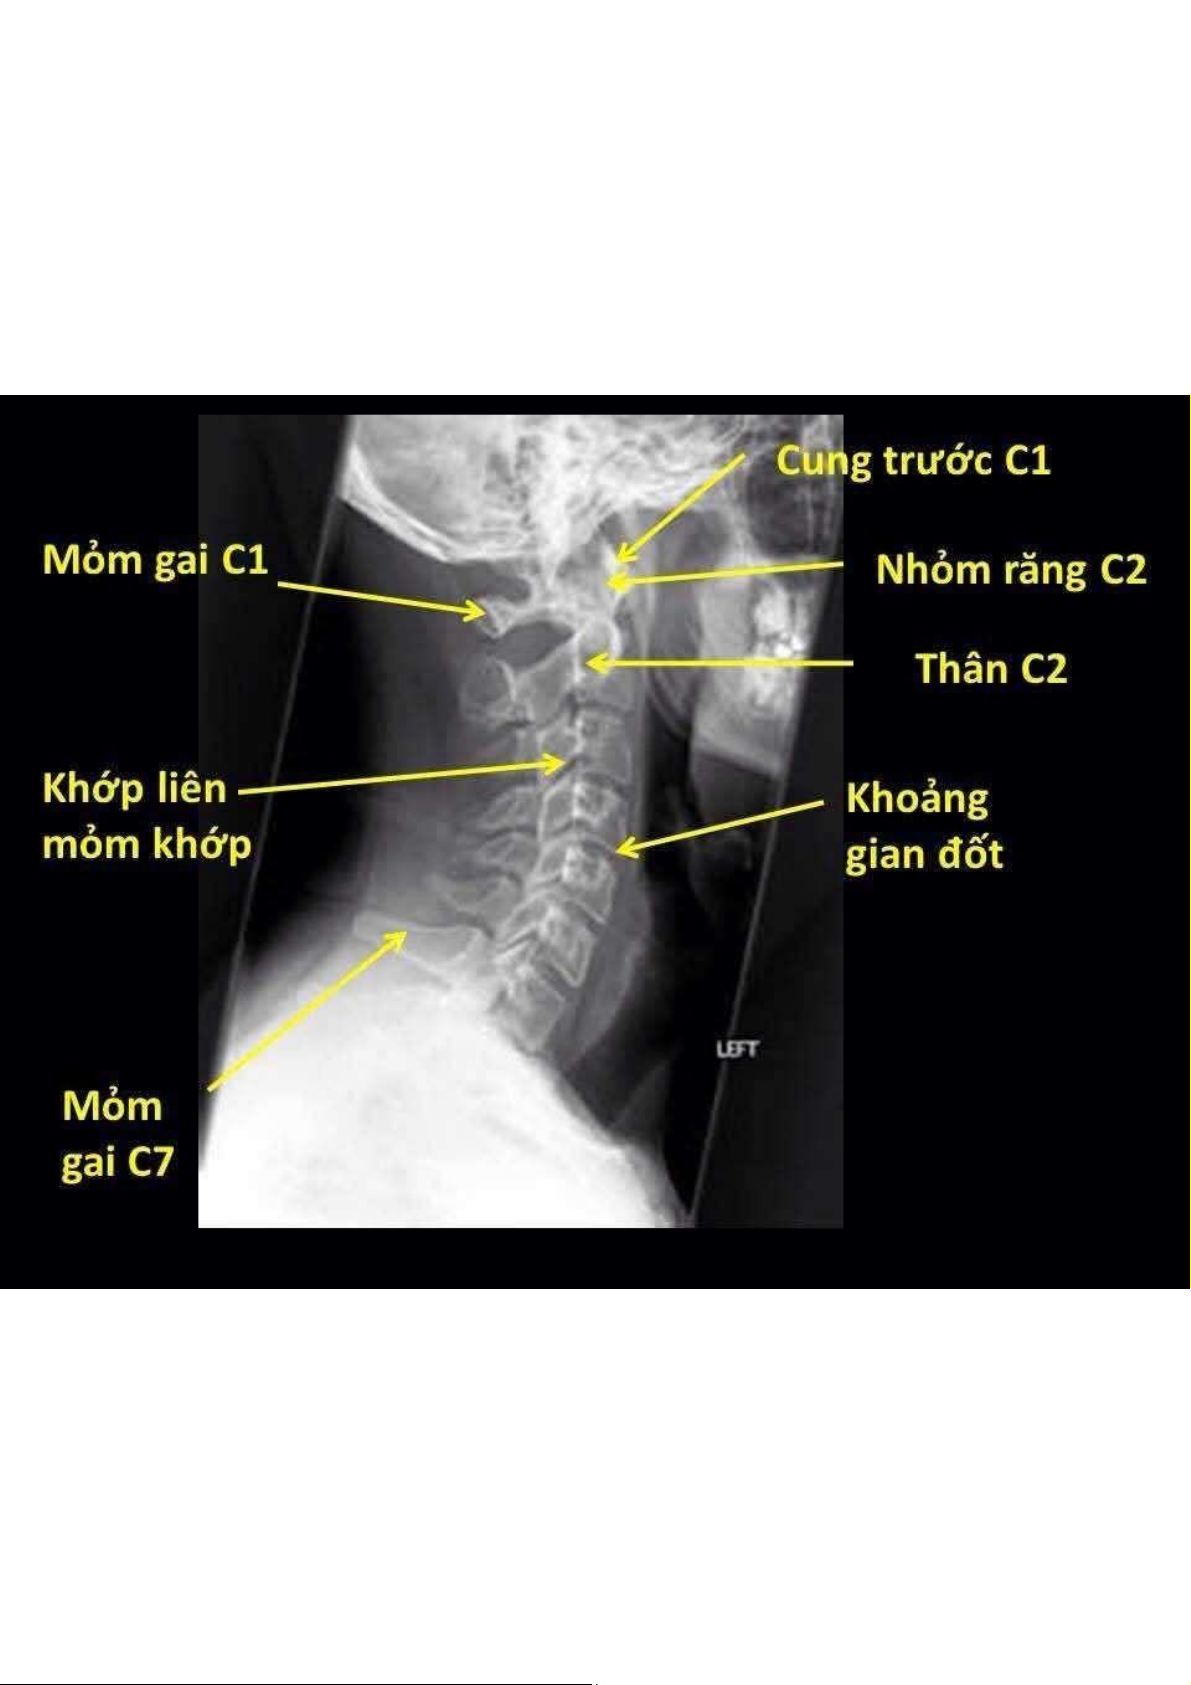

Gãy xương chày và mác dạng chồng ngắn. Gãy xương cánh tay dạng chồng ngắn và gập góp. Gãy xương quay dạng chồng ngắn và gập góp. Hẹp khoảng đĩa đệm. Xơ xương dưới sụn. Ngoài ra: kén dưới sụn, khí trong đĩa đệm, đóng vôi được dọc sau. Tài liệu giúp bạn tham khảo, ôn tập và đạt kết quả cao. Mời đọc đón xem!

Tài liệu Bài 6 X-Quang Xương Khớp - Phân Tích và Chẩn Đoán | Đại học Y dược Cần Thơ